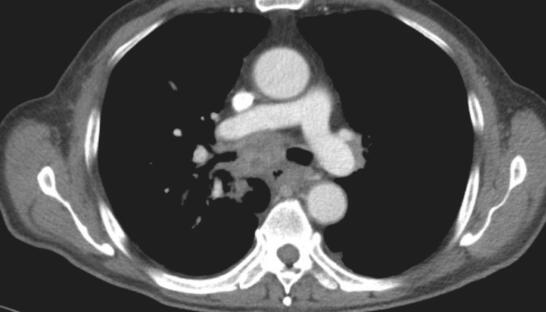

入院后检查:体温36.8℃,脉搏88次/分,呼吸22次/分,血压130/80mmHg。右侧锁骨上可扪及一绿豆大淋巴结,质中,活动度一般,无触痛,其余部位未及明显肿大淋巴结。轻度桶状胸。胸壁无肿块、无扩张血管;呼吸规整,双肺呼吸音粗,可及散在湿啰音及呼气相哮鸣音,未见杵状指(趾),双下肢无水肿。血常规正常、生化正常、肝炎标志物、梅毒+HIV抗体均阴性;类风湿因子、风湿因子阴性、结核抗体:阴性;8次结核涂片:荧光染色抗酸杆菌(-);G试验、血隐球菌乳胶凝集试验、血寄生虫抗体均阴性;3次痰涂片革兰染色未见细菌;血T-spot:(A抗原)20个、(B抗原)3个;血CD4+/CD8+正常。血管紧张素转化酶32IU/ L。肺功能:通气功能轻度减退(阻塞性),残气及残总比值增高,弥散轻度减退,气道阻力增高。FVC 2.16L(95.3%);FEV1 1.22L(69.4%);FEV1/FVC 56.72%。胸CT(2014年4月17日)示:两肺肺气肿,右肺下叶见团片状病灶,纵隔、肺门多发淋巴结肿大(图1和图2)。右下肺穿刺:见少许炎性细胞。右锁骨上淋巴结穿刺见少量炎性细胞及上皮样细胞。气管镜左总支气管新生物活检:重度慢性炎。气管镜右中间支气管刷检灌洗找结核肿瘤(-)。气管镜1R、2R、7组淋巴结E-bus穿刺见炎性细胞及少量坏死组织。

图2 2014年4月17日胸部CT

纵隔窗见纵隔、肺门多发淋巴结肿大